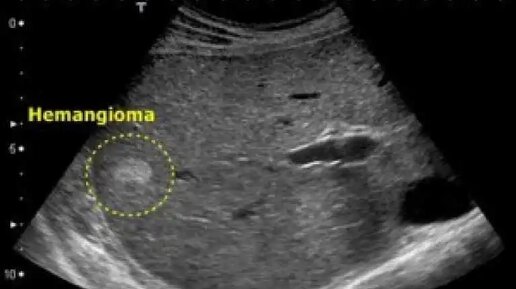

Гемангиомы — сосудистые образования, которые довольно часто встречаются на коже, но могут быть и на внутренних органах. Гемангиома (или ангиома) печени — скопление в печени сосудистых полостей, заполненных кровью. Это доброкачественное новообразование, которое не перерождается в рак и не распространяется на другие органы. Это довольно частая патология — встречается примерно у 5-15% людей в возрасте 30-50 лет, чаще у женщин. Обычно возникает одна гемангиома, хотя могут быть и множественные. Главное о гемангиоме печени рассказала Татьяна Владимировна Лученининова — врач высшей категории, к...

Эта статья написана после впечатляющего клинического случая гемангиомы у молодого мужчины, который вернулся из Китая домой, в Москву после длительной командировки. Закончилось все хорошо, подтвердили доброкачественное образование (подробнее писала в своем ТГ-канале на прошлой неделе). Однако, всегда ли можно сказать, что "хорошо"=доброкачественное образование? Очень надеюсь, что Вам поможет разобраться в ситуации моя статья, если у Вас на УЗИ выявлена гемангиома печени. Гемангиомы печени – это часто встречающиеся образования печени, которые носят доброкачественный характер...